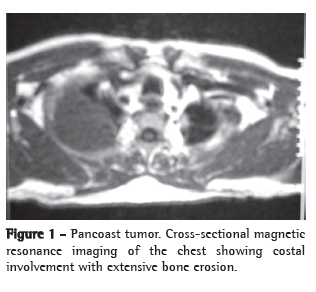

Laboratory tests presented the following results: creatine kinase levels of 898 U/L (ref. ≤ 174 U/L); aspartate aminotransferase levels of 76 U/L (ref. ≤ 35 U/L); antinuclear factor (ANF) in HEp-2 cells at 1:160 (fine dots); and nonreactive anti-SSA (Ro), anti-SSB (La), anti-Sm, and anti-RNP antibodies and rheumatoid factor. A chest X-ray showed a spiculated pulmonary nodule, with a diameter of 2 cm, in the left upper lung field. Computed tomography of the chest revealed a spiculated, dense nodule in the right pulmonary apex and presenting striations toward the pleura (Figure 1). The results of endoscopy of the upper digestive tract, bronchoscopy, and pulmonary function tests were normal. The results of the other relevant tests are presented in Chart 1.